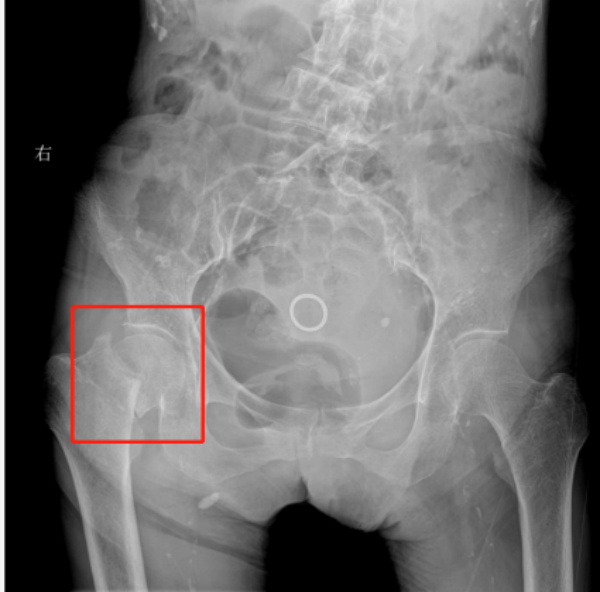

姜奶奶虽然已经101岁高龄,但平日里身体还算硬朗,生活基本能够自理。然而,一场意外的摔倒,让她的右侧股骨颈不幸骨折。家人紧急将她送往烟台业达医院骨科就诊,经检查确诊为右侧股骨颈骨折。

对于普通人而言,股骨颈骨折或许通过手术治疗便能逐步康复,但对于101岁的老人来说,这无疑是一场 “生死考验”。高龄患者身体机能衰退,而且常伴有高血压、冠心病、糖尿病等多种基础疾病,手术耐受度极低,术中术后发生心脑血管意外、感染、血栓等并发症的风险极高,甚至可能直接危及生命。因此,“是否手术” 成为摆在医疗团队和家属面前的一道难题:保守治疗需长期卧床,极易引发肺部感染、压疮、下肢深静脉血栓等严重并发症,死亡率高达 50%;手术治疗虽能让患者早期下床活动,降低卧床并发症风险,但手术难度和风险却超乎想象。

术前,各学科专家各司其职:心内科专家对老人的心脏功能进行全面评估,调整降压、护心药物,优化心脏状态;呼吸内科专家指导老人进行呼吸功能训练,预防术后肺部感染;麻醉科专家制定了精准的麻醉方案,既要保证手术顺利进行,又要最大限度减少麻醉对老人身体的影响;骨科团队则反复研究老人的影像学资料,精准测量所需假体尺寸、角度,制定详细的手术计划,力求手术操作“零误差”。